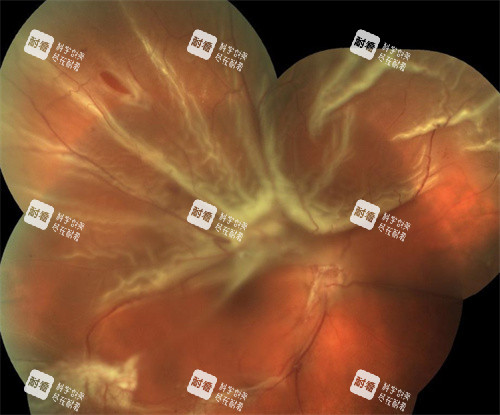

眼底病是眼科中较为复杂且严峻的一类疾病,如视网膜脱离、黄斑病变等,这些疾病不仅会严峻影响患者的视力,甚至可能导致失明。

眼底手术是一项高难度的手术,需要医生具备高度的专注力和比较准的操作技巧。

魏医生在每一台手术前,都会对患者的病情进行齐全的评估和分析,制定详细的手术计划。